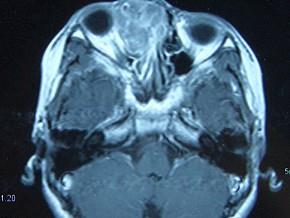

问题 女,16岁,鼻塞、流涕一年余,失去嗅觉,影像检查如图所示,最可能的诊断是 ( )

选项 A、小唾液腺癌 B、嗅神经母细胞瘤 C、筛窦癌 D、恶性淋巴瘤 E、鼻腔乳头状瘤

答案 B